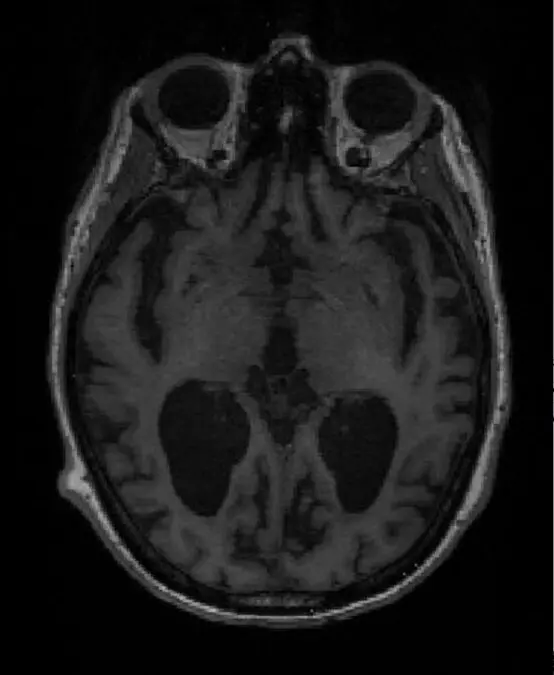

A team led by Professor Zoe Kourtzi at the University of Cambridge and The Alan Turing Institute has developed machine learning tools that can detect dementia in patients at a very early stage. Using brain scans from patients who went on to develop Alzheimer’s, their machine learning algorithm learned to spot structural changes in the brain. When combined with the results from standard memory tests, the algorithm was able to provide a prognostic score – that is, the likelihood of the individual having Alzheimer’s disease.

Professor Kourtzi, from Cambridge’s Department of Psychology, said: “We have trained machine learning algorithms to spot very early signs of dementia just by looking for patterns of grey matter loss – essentially, wearing away – in the brain. When we combine this with standard memory tests, we can predict whether an individual will show slower or faster decline in their cognition.

Although the algorithm has been optimized to look for signs of Alzheimer’s disease, Professor Kourtzi and colleagues are now training it to recognize different forms of dementia, each of which has its own characteristic pattern of volume loss.

Dennis underwent an MRI scan and later that same day he and Penny received the news that his results were consistent with early onset of Alzheimer’s disease. Dennis will begin taking medication to help treat the symptoms of Alzheimer’s disease.